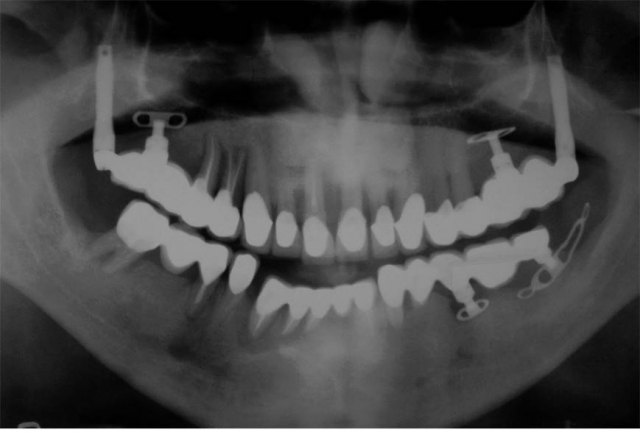

Despite a relatively high long-term survival rate, biological and technical complications are frequently encountered, and part of the problem is that as dentists, we sometimes fail to communicate that all potential outcomes are multifactorial.

All these factors contribute, to some degree, to the degradation or failure of restorative components and/or implants.

So, the real question that we should pose here is: Do we “cure” or do we manage patients with implants and implant-supported prostheses?